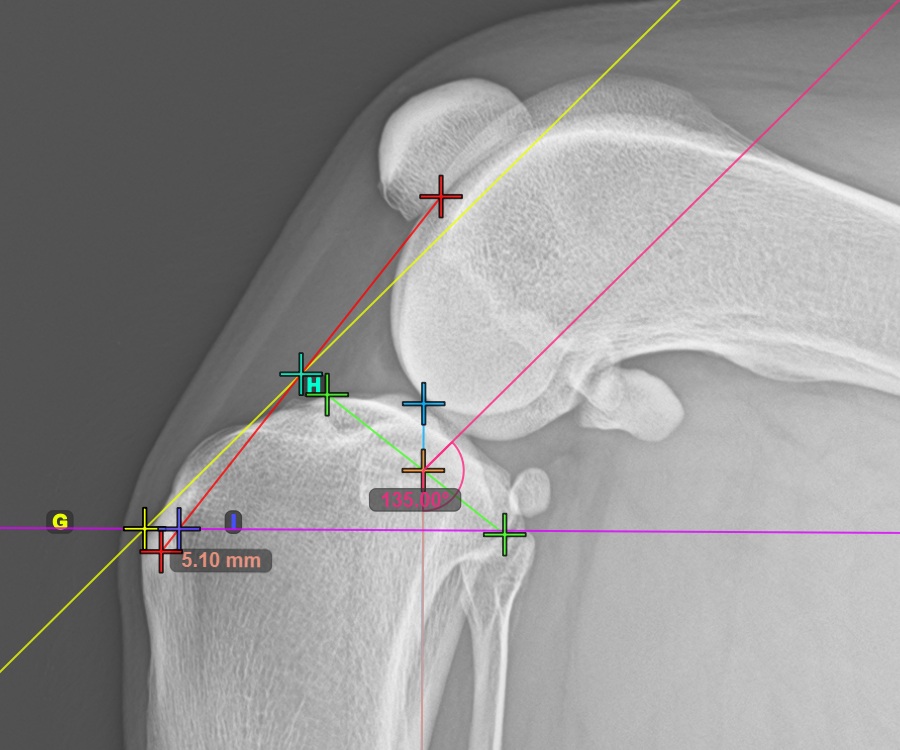

To complete the TTA Rapid variant of TTA measurement procedure mark the most dorsal point of the Crista Tibiae (Tuberositas Tibiae). The distance between the Tuberositas Tibiae and the automatic TTA Rapid helper lines is the required adjustment for the TTA procedure.

The image below depicts the usual placement of the tibial tuberosity, the most prominent point of the tibial crest.